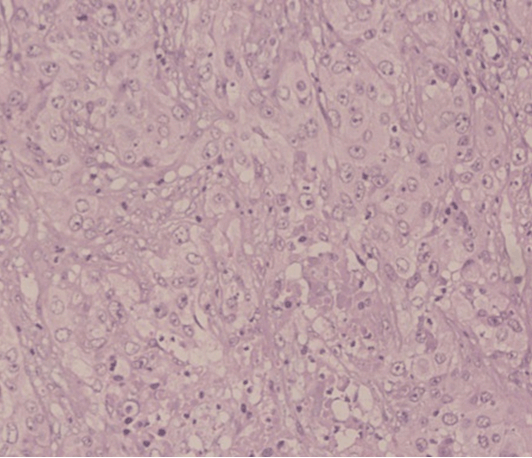

Figure 3: A squamous cell carcinoma of the bladder (H&E stain, x100).

Cursor on image to zoom/Click text to open image